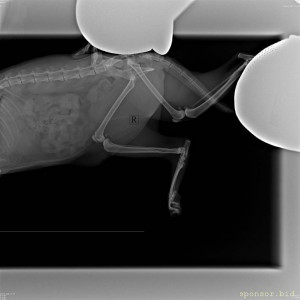

Кошке срочно нужна операция. Ходили на ренген. Перелом голени клиновидный диафизарный (смещение и перелом в 2 местах, фото прикладываю). Необходима операция методом некоторого остеосинтеза - установка пластины, стоимостью 22-24 тысячи рублей + узи сердца 1550 рублей, + предоперационное обследование 1500 рублей. У нас сейчас нет таких денег, операцию нужно проводить как можно быстрее, чтоб она не повредила ещё больше лапу. Прошу Вас, надежда на Вас.

Помогите собрать на операцию кошке - IMG-20230310-WA0027.jpg

Помогите собрать на операцию кошке - upload_2023_03_11_00_28_09_368.jpg